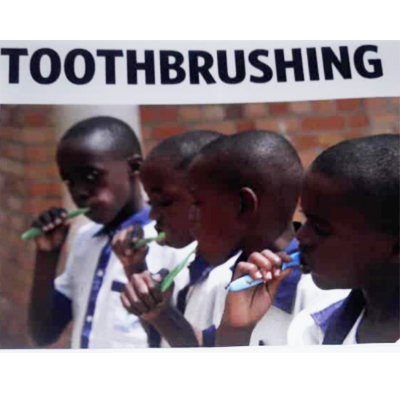

Oral Health Solutions Organization (OHSO), founded in October 2019, is an active non-governmental organisation (NGO) at the forefront of improving oral health in Rwanda, through oral health promotion, oral disease prevention and advocacy. The NGO vies to complement adequately Government effort to promote health and prevent diseases through school and maternal health settings. We adopt proactive engagement across all platforms in working alongside various government ministries, institutions,NGOs,dental professionals and the public.